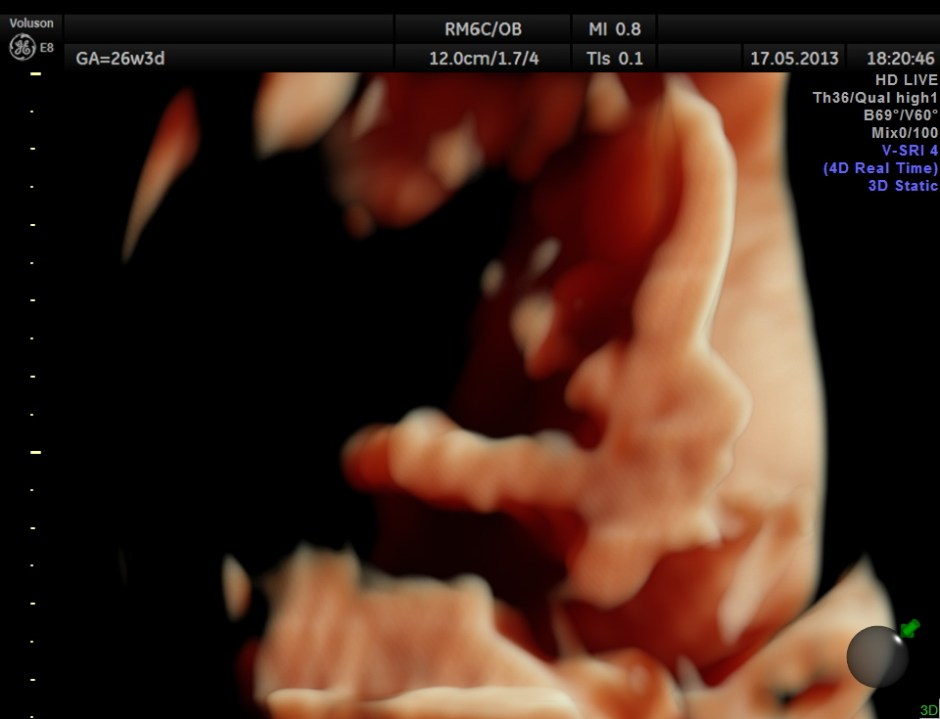

The following images show the face and the palate.

This fetus did not show any oro-facial clefts ; heart and spine appeared normal.